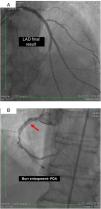

On 22 March, 2016, the patient returned for RCA PCI (Figure 2A). The proposed strategy was RA in the PDA and RPLA with a 1.5 mm burr, followed by implantation of two DES. Through right femoral access and a 7F JR guide catheter we crossed the RotaWire extra support through the RPLA lesion, then conducted three successive 20-s passes at 170 000 rpm successfully and uneventfully. As there were no signs of dissection and TIMI 3 flow was maintained, the 0.009″ RotaWire was repositioned to cross the PDA lesion and debulking of the lesion was performed. After two attempts with short, gentle movements we succeeded in crossing the lesion, however entrapment of the burr ensued (Figure 2B). The system was pulled back without success considering that the stretching of the system was causing wrinkles at the RCA and the 7F JR was penetrating deep into the artery, with risk of rupture. Attempts were then made to release the Rotablator, in both rotablation and dynaglide modes, by moving it forward and backward, but the burr did not even spin. Attempts were made to advance a parallel guidewire with 1.25 mm balloon but it did not progress within the 7F guide catheter. We therefore decided to puncture the left (contralateral) femoral artery and insert a 6F JR guide catheter to the RCA ostium, parallel to the first 7F guide catheter, and advance a PT2® guidewire (Boston Scientific) to the PDA branch with a 1.25 mm×8 mm balloon upstream to support this wire. We succeeded in arriving parallel to the Rotablator system until the proximal portion of the entrapment site. Attempts to cross the guidewire and balloon angioplasty tangentially to the burr were unsuccessful because the tip of the wire was not sufficiently stiff to cross it. When the PT2 was pushed with the back support of the balloon this forceful movement caused the tip of the wire to bend, and finally the guidewire was advanced with the ‘knuckle’ technique (used for recanalization of CTOs), taking advantage of the kinking of the distal portion of the PT2 guidewire, making a subintimal dissection. At this time we could not see if the wire had re-entered the true lumen, but the 1.5 mm balloon could then easily be crossed parallel to the burr and inflated to 16 atm to release the trapped burr (Figure 3A). The burr was subsequently withdrawn maintaining the RotaWire in the initial position. After administration of 100 μg nitroglycerin, angiography confirmed that the PT2 guidewire had re-entered the true lumen and reached the most distal part of the PDA. The RotaWire was pulled out together with the whole 7F system. Through the 6F system and the same PT2 wire, PCI was finalized with implantation of the two programmed 2.75 mm×20 mm and 2.75 mm×16 mm DES at 12 atm in the PDA and RPLA, respectively, without any further predilation. We also noted the presence of a long and severe dissection in the mid third of the RCA, certainly caused by excessive handling and attempts to remove the burr, which caused deep penetration by the 7F guide catheter. This dissection was promptly corrected with implantation of a third 4.0 mm×32 mm DES, and final TIMI 3 flow was obtained without clinical or electrocardiographic complications (Figure 3B). The two femoral puncture sites were occluded with 8F and 6F AngioSeal devices, respectively. The patient remained in the intensive care unit for 48 hours, the only abnormality being CK-MB elevation (twice the reference value). He was discharged on day 3 in excellent general condition. The control echocardiogram showed normal left ventricular contractility.

(A) Percutaneous coronary intervention of the left main and left anterior descending artery (LAD) with two overlapping drug-eluting stents (DES) and the second diagonal branch with another mini-crush DES after rotablation with 1.5 mm burr, and ultimate success (TIMI flow 3); (B) burr entrapment in the posterior descending artery (PDA). The stiffness of the system when pullback was attempted is evident (arrow).